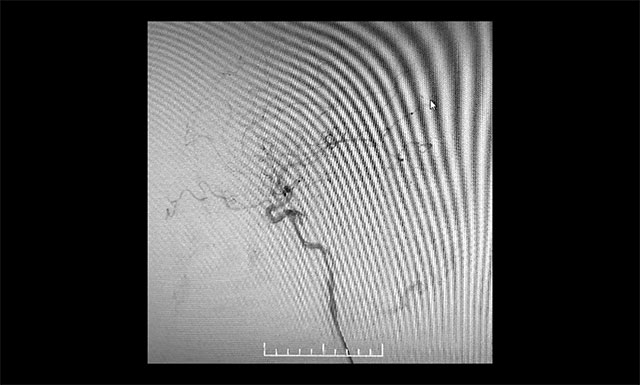

▲ 术毕左侧颈内动脉造影

▲ 术毕左侧颈外动脉造影